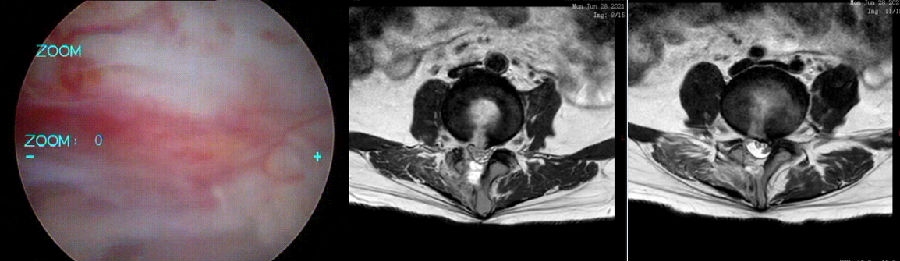

四、硬膜外血肿(2.27%)

具有神经系统症状需要处理的血肿发生率仅为0.6%,通常在术后24h内便会表现出术区的剧烈疼痛,伴随神经根性症状、肌力缺失和感觉障碍。

图片来源:Yi S, Yoon DH, Kim KN, Kim SH, Shin HC. Postoperative spinal epidural hematoma: risk factor and clinical outcome. Yonsei Med J. 2006 Jun 30;47(3):326-32.

椎管内血肿分级:

Grade 0:无血肿

Grade I:占椎管面积<25%

Grade II:占椎管面积25%-50%

Grade III:占椎管面积 50%-75%

Grade IV:占椎管面积 >75%

图片来源:Kim Ju-Eun,Yoo Hyun-Seung,Choi Dae-Jung et al. Effectiveness of Gelatin-Thrombin Matrix Sealants (Floseal®) on Postoperative Spinal Epidural Hematoma during Single-Level Lumbar Decompression Using Biportal Endoscopic Spine Surgery: Clinical and Magnetic Resonance Image Study.[J] .Biomed Res Int, 2020, 2020: 4801641.

病例

男,64岁。

主诉:腰痛2年、加重伴左下肢疼痛麻木4个月,左小腿后外侧为著。

术后复查